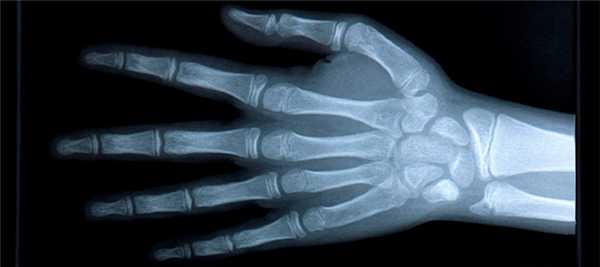

Назначение снимка — изучение скелета кисти в целом, включая запястье, пястье и фаланги.

Укладка больного для выполнения снимка. Больной сидит боком к краю стола. Рука отведена, согнута в локтевом суставе; кисть находится в положении пронации. Пальцы выпрямлены и сомкнуты.

Кассета размером 18Х 24 см расположена в плоскости стола. Ладонь плотно прилежит к кассете.

Средней поперечной линии кассеты соответствует проекция головок пястных костей.

Пучок рентгеновского излучения направлен отвесно на головку III пястной кости (рис. 367).

Информативность снимка. На снимке выявляются дистальные метаэпифизы костей предплечья, рентгеновская суставная щель лучезапястного сустава, запястье, пястные кости и фаланги. Хорошо видны рентгеновские суставные щели мелких суставов кисти.

При правильно подобранных физико-технических параметрах съемки четко видна губчатая структура костей запястья, концов пястных костей и фаланг. В телах коротких трубчатых костей определяются мозговые полости и корковое вещество (рис. 368).